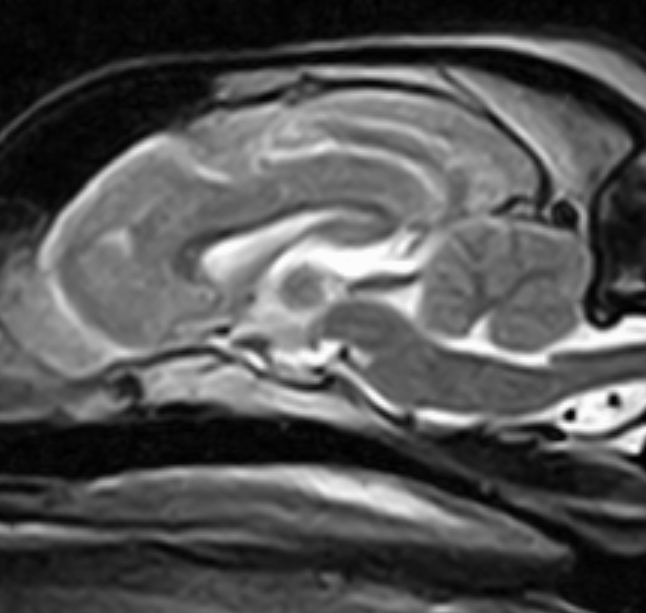

Dentro de CENEV contamos con especialistas dedicados al área de imagenología, dedicados al diagnóstico por pruebas como ultrasonido abdominal, radiología de tórax y abdomen, entre otras.

Nuestros equipos y personal especializado permiten estudios rápidos y de alta calidad para apoyar el diagnóstico clínico.